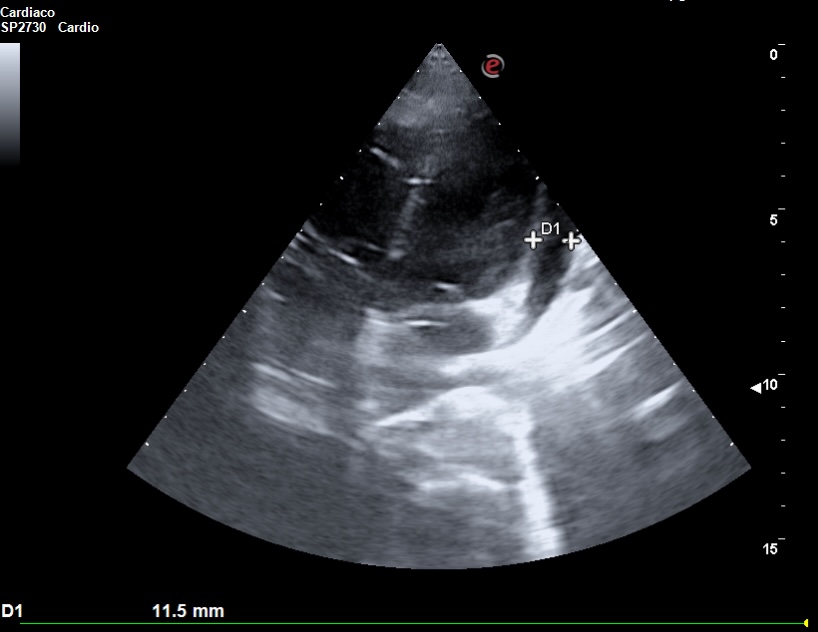

La ecocardioscopia mostró ventrículo izquierdo no dilatado con función sistólica conservada, sin hipertrofia del septo interventricular ni valvulopatías. Aurículas izquierda y cavidades derechas de tamaño normal. TAPSE normal. Se evidenció un derrame pericárdico moderado sin signos de taponamiento cardíaco. Calibre de vena cava inferior normal con colapsabilidad mayor del 50%. Hallazgo de derrame pleural derecho moderado.

La ecografía clínica desempeñó un papel fundamental en la evaluación inicial del paciente, permitiendo una detección rápida y precisa de hallazgos que guiaron la toma de decisiones clínicas. La ecocardioscopia realizada reveló un derrame pericárdico moderado, sin signos de taponamiento cardíaco y un derrame pleural derecho significativo. Estos hallazgos fueron esenciales para descartar la presencia de un cuadro obstructivo que pudiera haber requerido una intervención inmediata. Además, la ecografía permitió valorar el estado hemodinámico de la paciente de forma no invasiva, asegurando que el derrame pericárdico no comprometiera la función cardíaca. En la radiografía de tórax se objetiva una masa mediastínica. La capacidad de detectar y cuantificar de forma precisa tanto el derrame pleural como el pericárdico sin necesidad de esperar a pruebas más complejas, permitió que la paciente fuera ingresada de manera adecuada para un estudio exhaustivo y sin demoras innecesarias.